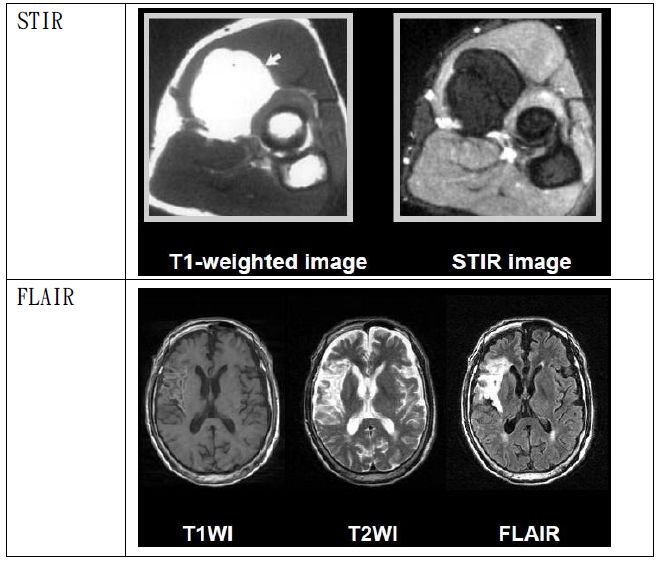

STIR :抑制脂肪FLAIR :抑制水

STIR Short TI inversion Recovery(TI反轉回復):

利用RF加在X軸,使磁矩在Z軸直接反轉,並等待組織成份進行recovery,通過“null point”之後才開始造影。例如:想抑制脂肪,就等脂肪通過null point再開始造影。然而在90°RF 脈衝之前先給予180°RF脈衝,這段時間稱之TI(inversion time)。脂肪屬於短TI,適當設定TI,即可抑制脂肪訊號,因此在影像上會是暗訊號。同理當抑制對象是水時,此方式稱“FLAIRfluid attenuated inversion recovery(流體稀釋反轉回復)